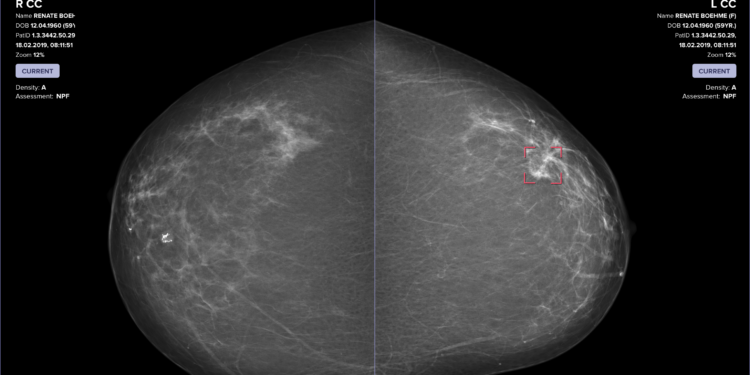

Image showing Vara's AI SaaS platform and how it works with breast cancer screening technology.

Images showing Vara’s AI SaaS platform and how it works with breast cancer screening technology.

Provided by Vara.

Vara’s software platform works across the workflow of a radiologist. Muff says Vara uses AI on multiple fronts. The software platform works to seamlessly filter out normal cancer-free mammograms, so the radiologist can spend more time focusing on and analyzing screenings that may have suspicious aspects. Additionally,  Vara’s technology also alerts the radiologist in case they missed a potential case of cancer that might be otherwise overlooked. Muff said the team refers to this feature as Vara’s “safety net,” which, via its AI and machine learning, may more quickly spot potential cancer.